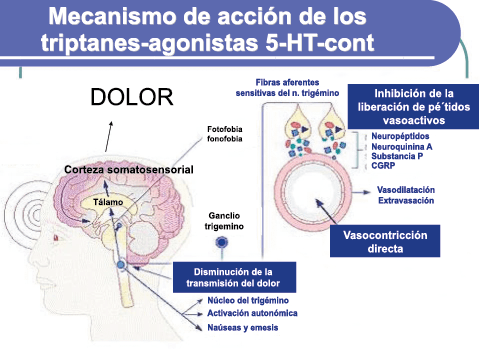

Posteriormente diversos estudios demostraron que la infusión de 5-HT podría abortar tanto la cefalea inducida por reserpina(55) como la espontánea(56). En respuesta a estos estudios, el sistema del receptor 5-HT ganó mucha atención, lo que culminó con el descubrimiento de los triptanos, la serotonina y los agonistas del receptor 5-HT1B/1D(57). Todos exceptuando el 5-HT3 (canal iónico controlado por ligando) son receptores acoplados a proteína G. Si bien los triptanos se clasifican como agonistas de los receptores 5-HT1B/1D, la mayoría también activa en menor medida los receptores 5-HT1A, 5-HT1E o 5-HT1F(58). Originalmente, los triptanos se desarrollaron para actuar sobre la vasculatura craneal, una idea apoyada por sus claras acciones vasoconstrictoras(59) (Figura 25) y la expresión preferencial del receptor 5-HT1B en los vasos craneales más que en los periféricos(60).

Un mecanismo neural de los triptanos en las terminaciones del nervio trigémino periférico podría inhibir la liberación de neuropéptidos proinflamatorios y la vasodilatación dural neurogénica(63), lo cual era consistente con el tema en desarrollo de la migraña como una enfermedad neurovascular. (Figuras 26 y 27)

En la figura 28 se muestra un resumen de los fármacos y sus mecanismos de acción en el contexto del sistema trigémino vascular.